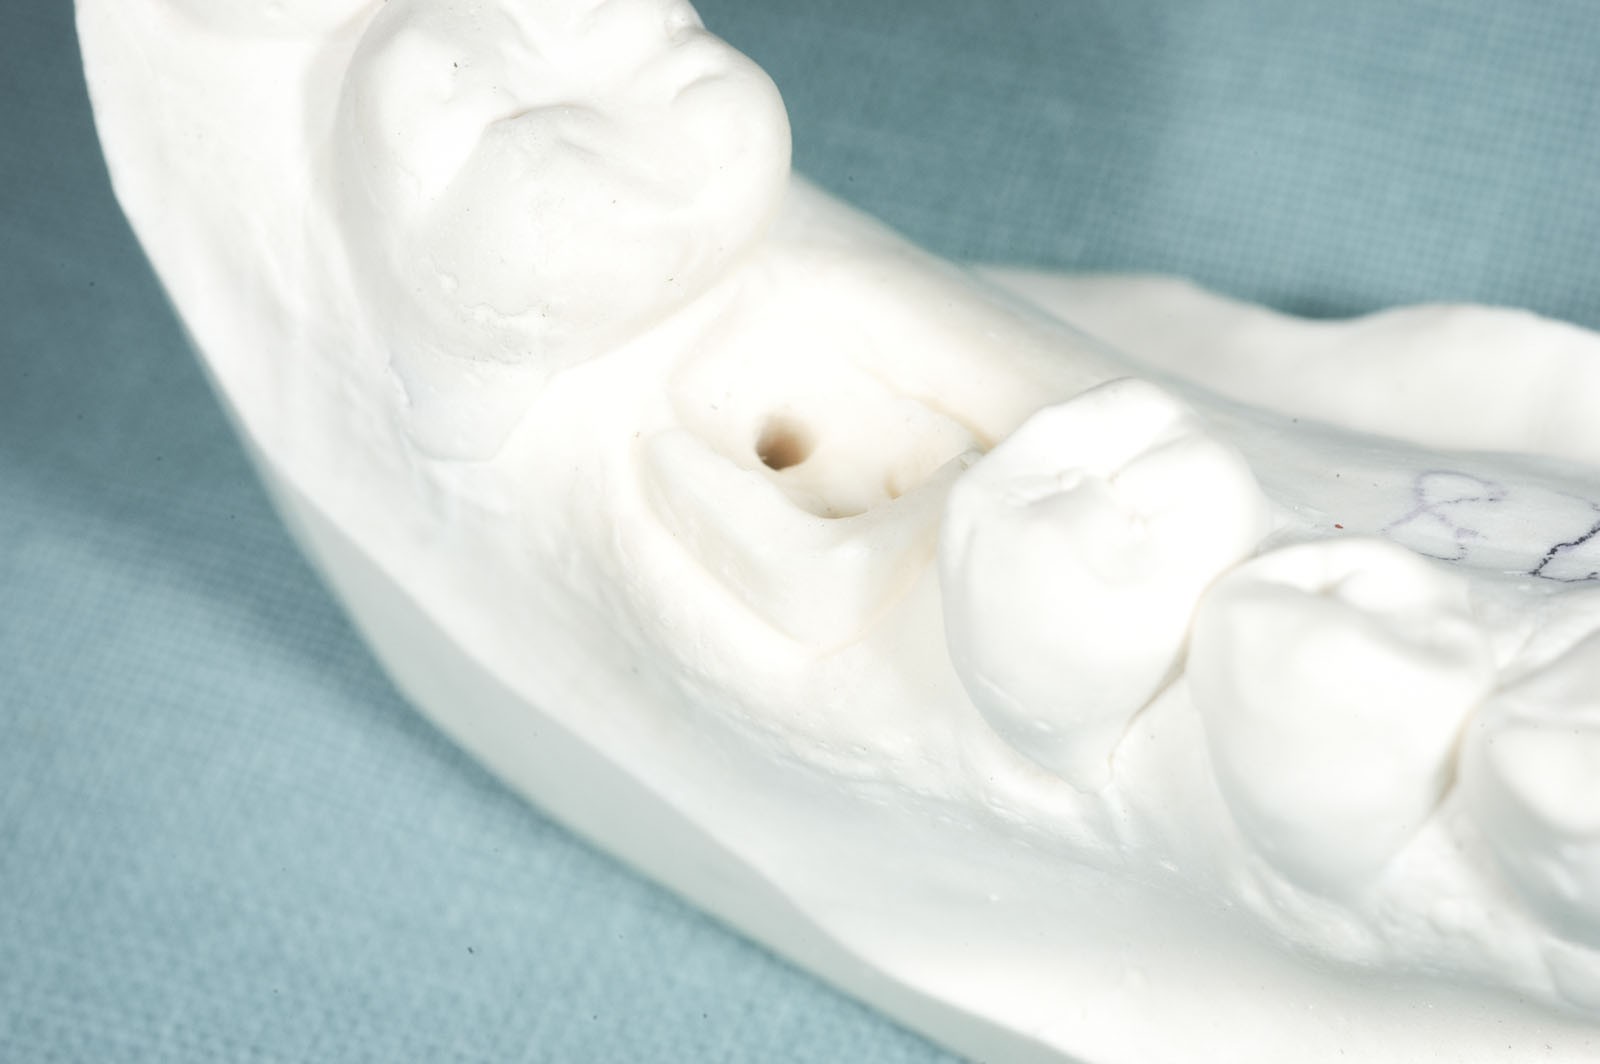

Wkłady koronowo-korzeniowe to rusztowanie dla korony zęba. Ich zadaniem jest jego wzmocnienie. Stosuje się je w zębach leczonych kanałowo, w których doszło do dużego zniszczenia struktur korony zęba.

Wskazaniem do wykonania wkładów koronowo-korzeniowych jest wzmocnienie zęba leczonego kanałowo, w którym doszło do powstania dużego ubytku w jego części koronowej. Jeżeli ząb ma niewiele tkanek własnych lub są one uszkodzone, grozi to powstaniem naprężeń, w wyniku których może dojść do odłamania się jego ścian. Wkłady koronowo-korzeniowe zapobiegają uszkodzeniom mechanicznym zębów.

- Wkłady koronowo-korzeniowe – przeznaczone dla zębów po leczeniu kanałowym, których konstrukcja wymaga wzmocnienia ze względu na stopień jej uszkodzenia. Wkłady wykonywane są w laboratorium protetycznym lub w gabinecie stomatologicznym i montowane wewnątrz kanału korzeniowego zęba. Wkłady laboratoryjne to indywidualnie odlewane elementy ze stopów metali, podczas gdy w gabinecie używa się wykonanych z włókien syntetycznych.